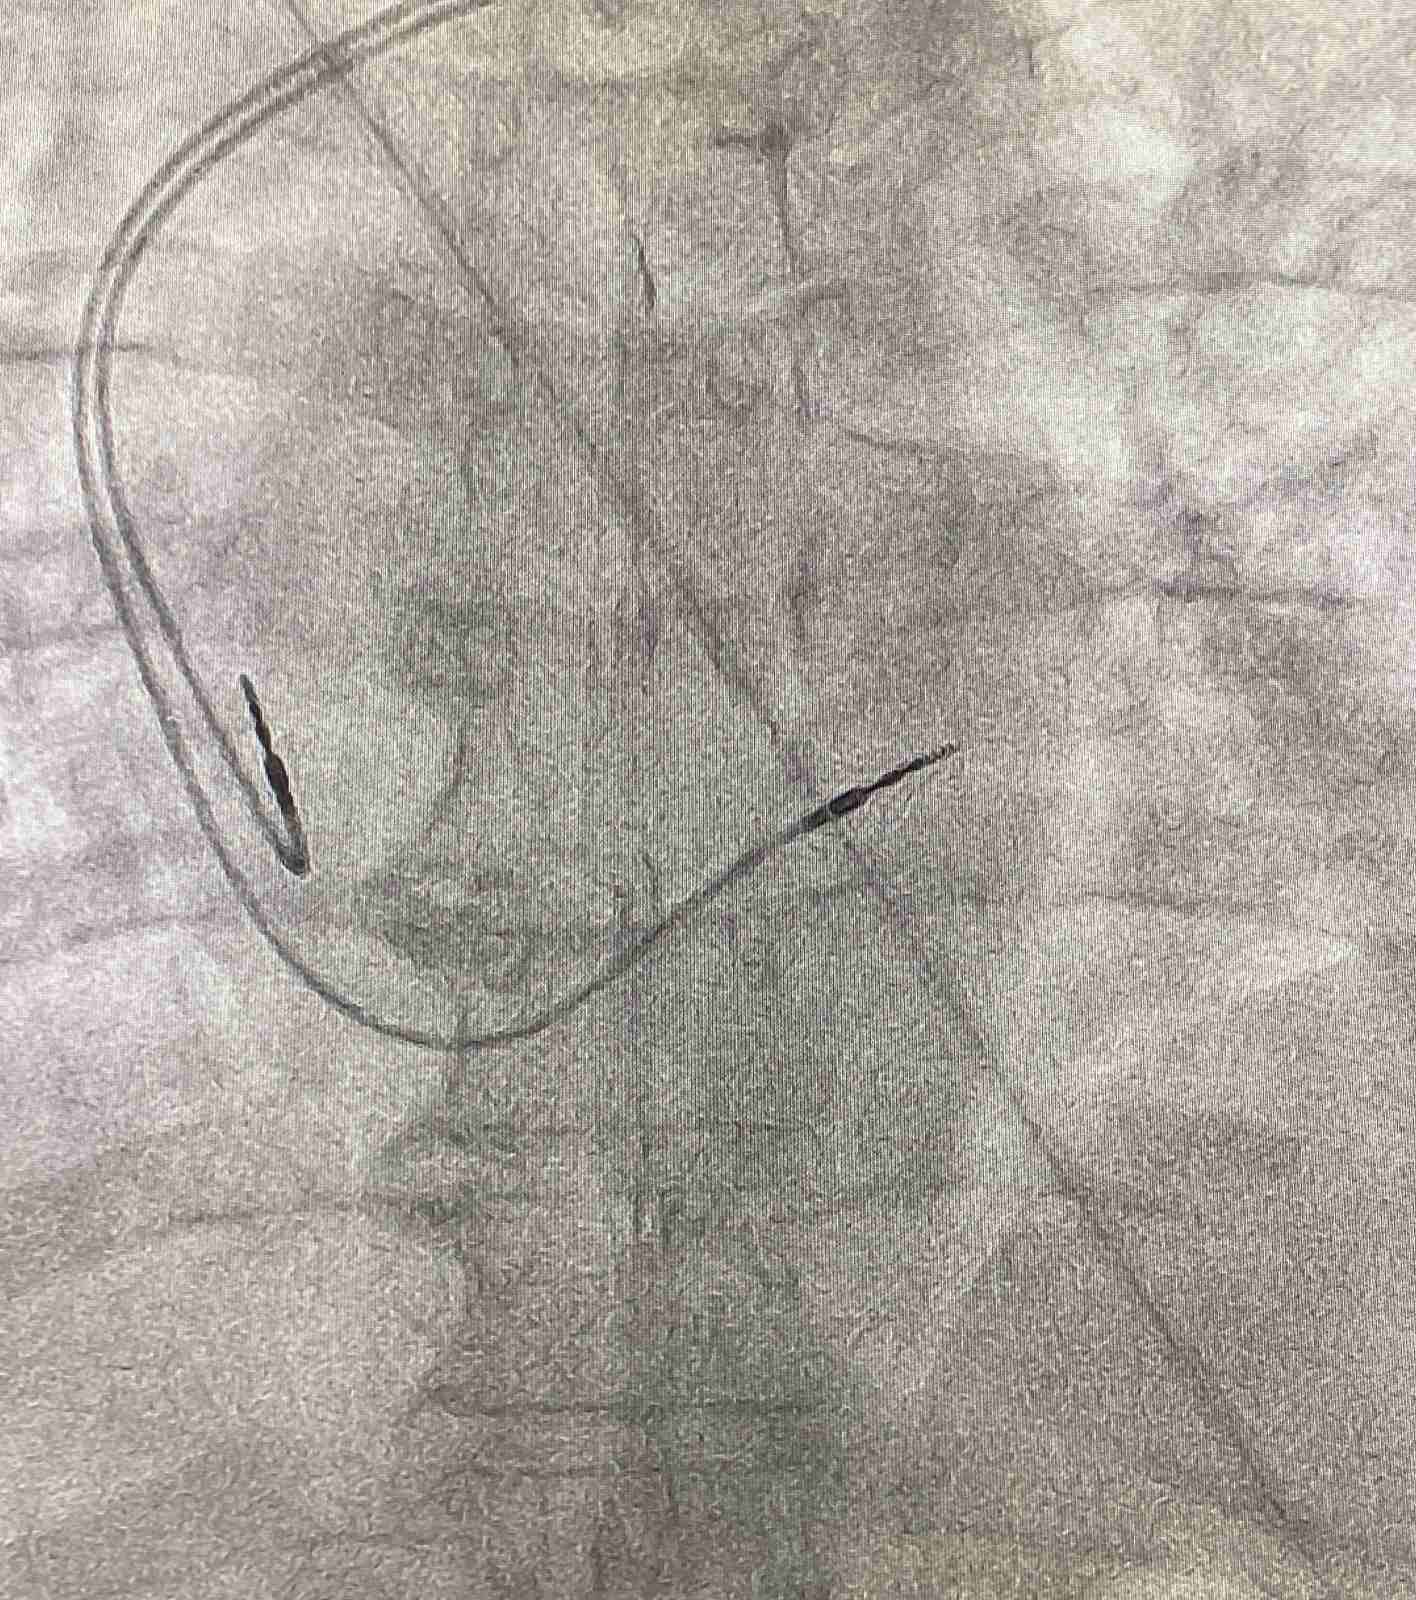

На базе регионально-сосудистого центра Клинической больницы № 6 имени Г. А. Захарьина, который является участником реализации мероприятий федерального проекта «Борьба с сердечно-сосудистыми заболеваниями» национального проекта «Здравоохранение» за апрель 2023 года было имплантировано 9 электрокардиостимуляторов пациентам с брадиаритмиями и синкопальными состояниями.

«Все стимуляторы, имплантируемые в нашем лечебном учреждении, являются частотноадаптивными, т.е. увеличивают частоту сердечных сокращений в зависимости от интенсивности физической нагрузки и используют технологию MRI sure scan, которая разработана для безопасного использования МРТ при необходимости», - поясняет заведующий РСЦ Дмитрий Максимов.